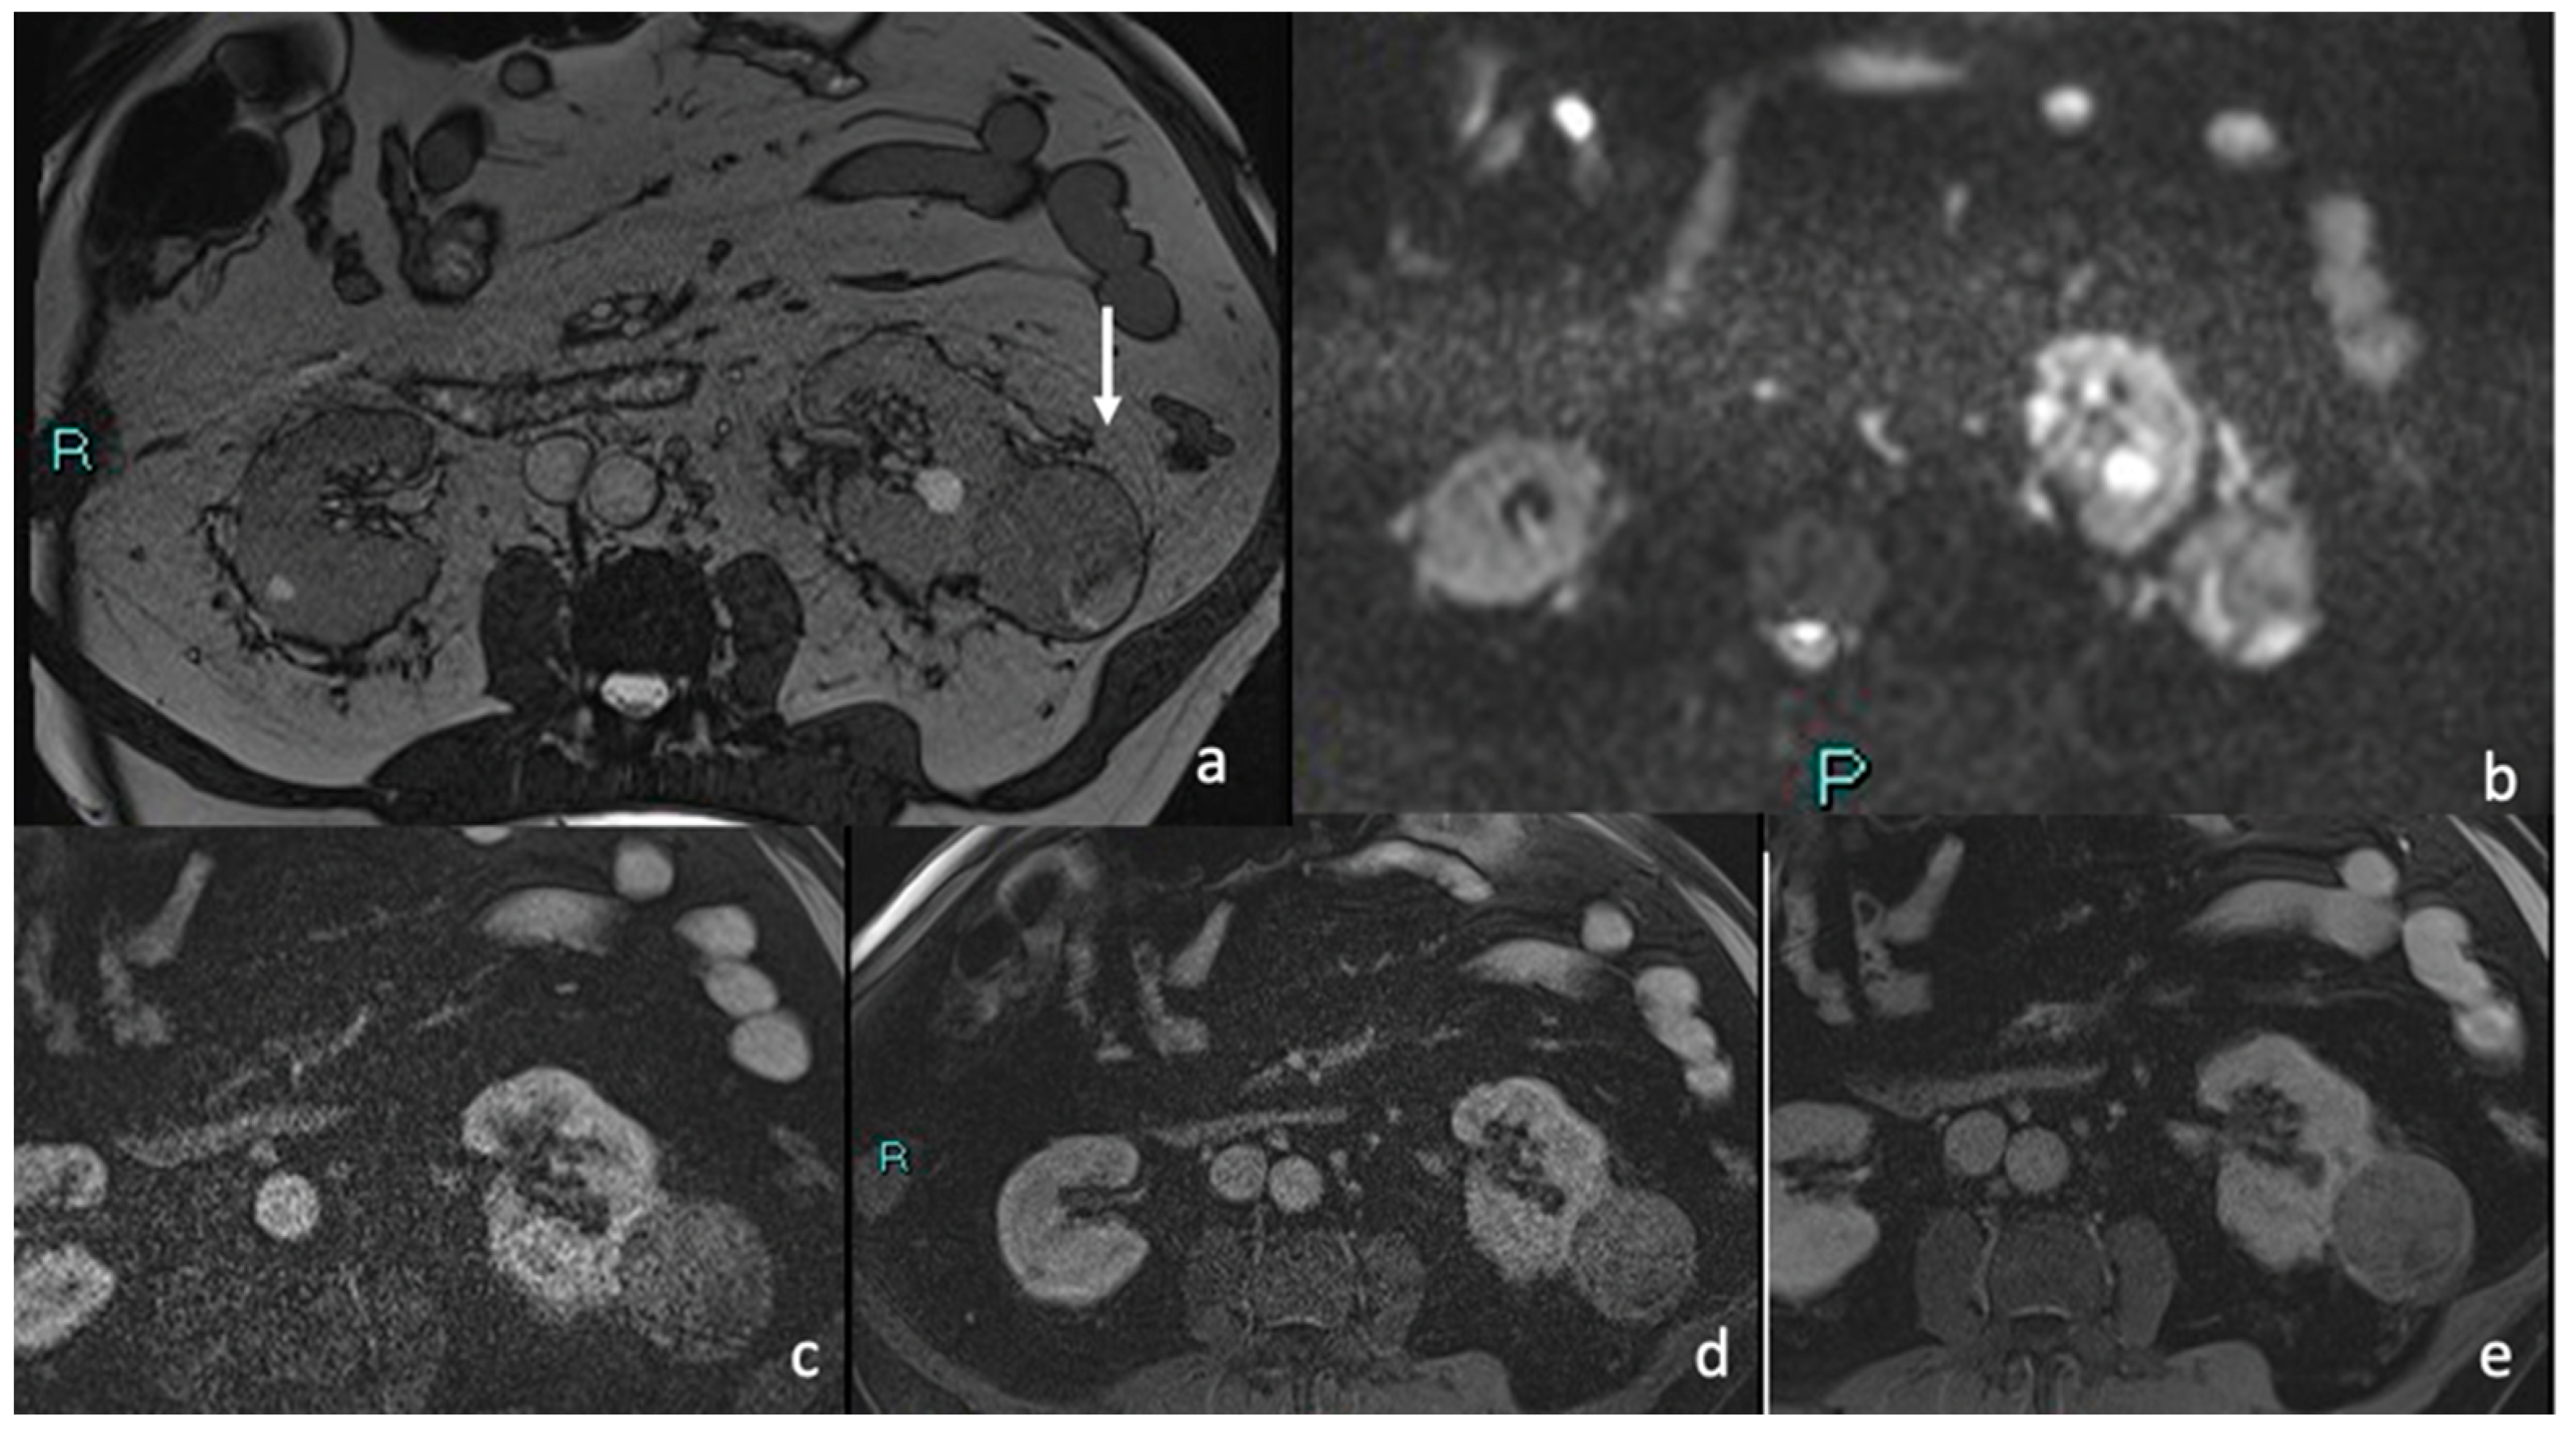

3.4. MRI

Signal Intensity, Homogeneity, and Contrast Enhancement

| MRI FEATURES | % | n. | p Value |

|---|---|---|---|

| 85.2% 14.8% | 23 4 | p < 0.05 p > 0.05 |

| 88.9% 7.4% 3.7% | 24 2 1 | p < 0.05 p > 0.05 p > 0.05 |

| 29.6% 11.1% 59.5% | 8 3 16 | p > 0.05 p > 0.05 p < 0.05 |

| 100% | 27 | p < 0.05 |